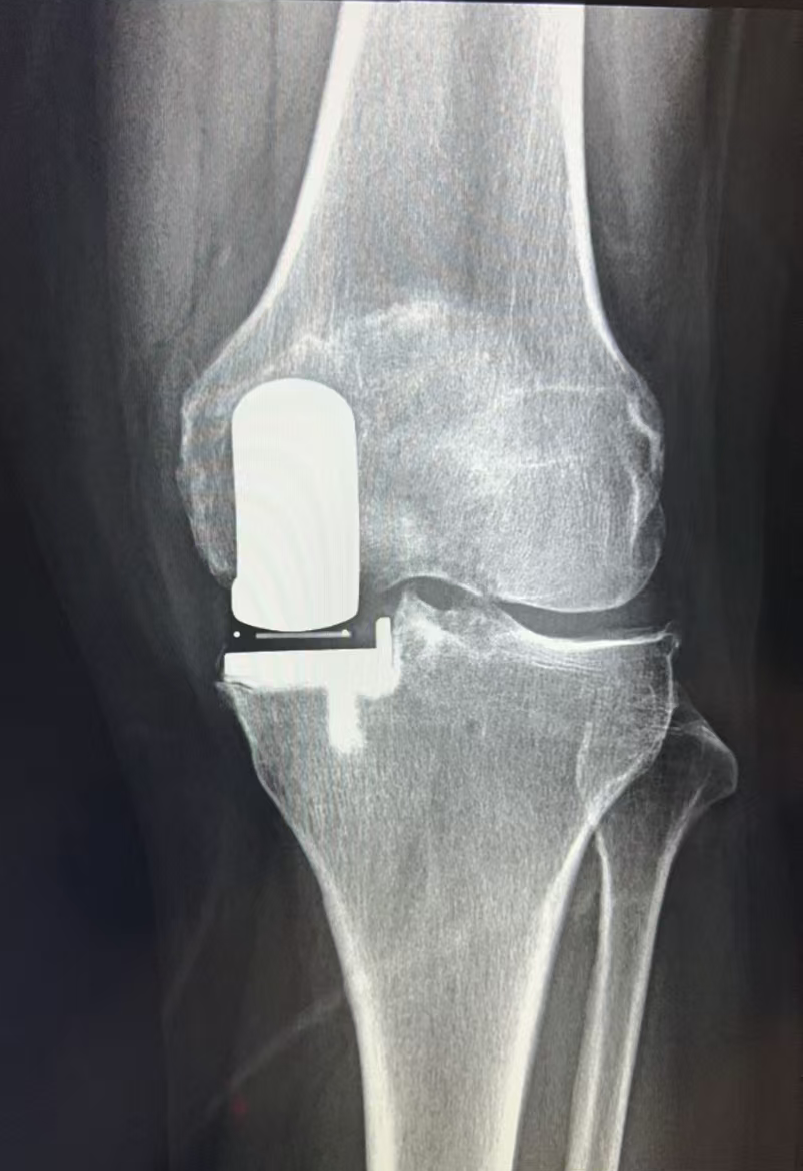

经过仔细评估,王歆峰主任决定给王阿婆做“左膝内侧单髁表面置换术”!这就是保膝治疗的一种,简单说,就是只修复膝盖磨损的那一部分,不用把整个膝盖关节换掉,创伤小、恢复快,还能保留膝盖原本的功能。

让王阿婆和家人都没想到的是,手术特别顺利,术后第二天,王阿婆就能下地慢慢行走了!王阿婆开心地说:“早知道有这么好的方法,我就不拖这么久了,之前连保膝是什么都不知道,还以为只能换膝盖,真是太感谢你了!”

什么是保膝治疗?

保膝治疗,就像是给磨损的膝盖“修修补补”,而不是“全盘替换”。它针对的是膝盖局部磨损的部位,保留膝盖其他健康的组织和功能。这样一来,手术创伤小,出血少,术后恢复也快,很多患者术后一两天就能下地行走,不用长时间卧床遭罪。